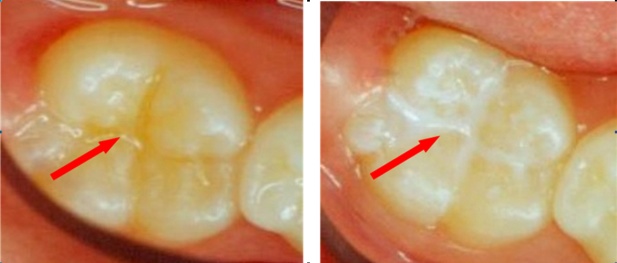

Οι προληπτικές καλύψεις οπών και σχισμών είναι υγρές ρητίνες οι οποίες τοποθετούνται στις μασητικές επιφάνειες των οπισθίων δοντιών. Σκοπός τους είναι να προστατέψουν το δόντι από την εμφάνιση τερηδόνας, εξαιτίας της κάλυψης που παρέχουν στις στενές οπές και σχισμές των δοντιών. Αυτό έχει ως αποτέλεσμα τον καλύτερο καθαρισμό με την οδοντόβουρτσα και την αποφυγή συσσώρευσης τροφών και μικροβίων στις περιοχές αυτές. Η προστασία που παρέχουν οι καλύψεις εφόσον παραμείνουν στη θέση τους είναι 100%.

Πότε και πώς γίνεται η τοποθέτησή τους;

Η τοποθέτησή τους γίνεται όταν έχει ολοκληρωθεί η ανατολή του δοντιού στο στόμα του παιδιού, οπότε η ηλικία που γίνεται η εφαρμογή τους διαφέρει από παιδί σε παιδί ανάλογα με το ρυθμό ανατολής των δοντιών του. Η τοποθέτησή τους είναι απλή και γρήγορη χωρίς να χρειάζεται αναισθησία ή τροχισμός του δοντιού. Εξίσου σημαντική είναι και η παρακολούθηση από τον παιδοδοντίατρο, διότι μερικές φορές οι προληπτικές καλύψεις μπορεί να αποκολληθούν από το δόντι, οπότε χρειάζεται η επανατοποθέτησή τους.

Οι προληπτικές καλύψεις οπών και σχισμών θα πρέπει να είναι μέρος ενός ολοκληρωμένου προληπτικού προγράμματος και να συνδυάζονται με τακτικές εφαρμογές φθορίου, ώστε να επιτυγχάνεται ακόμη μεγαλύτερη προστασία από την τερηδόνα.